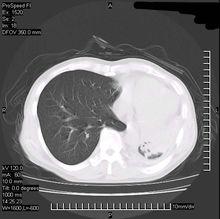

肺透明膜病CT圖

1.放射學檢查 先天性肺氣腫可見病變上葉多見,以左側為主下葉極少見特徵為單葉肺透亮度增加、血管紋理減少患葉體積明顯增大、鄰近健肺受壓、不張,縱隔健側移位膈肌下移或正常,透視可見縱隔吸氣時移向患側,呼氣向健側移位。偶爾也可見到患肺密度增加,而不是高透亮度,這是因為繼發於支氣管梗阻的液體排空障礙,但其他放射學所見的特徵仍存在,液體可在24h到2周內清除此後放射學特徵(高透亮度)恢復。特異性肺氣腫X線表現為患肺透亮度增加、肺門血管紋理減少。支氣管造影:支氣管近端充盈,遠端細小5~6級以下支氣管不充盈透視見:吸氣時縱隔患側移位,患側膈肌活動度減弱,患肺容積不隨呼吸運動而改變